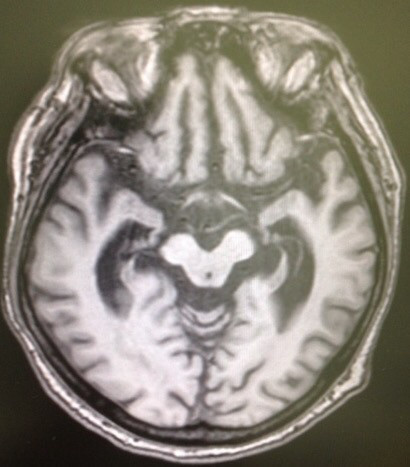

2018/09/18 MRIでも◯◯だから、CTなんて❌❌

もう、15年以上(もっとかも)、診療してきた80歳代 女性。お付き合いが長くなりました。

今回、ちょっとしたキッカケがあり、MRI撮影となりました。認知機能に問題なく、年に何回か(つい最近も)、海外に一人で行って来る方。長年の高血圧もあり、降圧剤を処方していますが、コントロール状況は良好。でも、最近の言動は昔より、何だか、自己否定的。鬱っぽい・・・。もともと、アタマの回転の良い方。御両親も、お子様も医療関係者。

色々な悩みも聞いてきたので、些細な言動でも、なんと無く気になる・・・。MRIの結果。前頭葉が萎縮している‼️

ピッ◯切痕がある‼️🤣医療で、絶対なんてあり得ない。そりゃ否定しません。が・・・この方の場合、自信をもって言えますが、

“一部の医者”が乱発しているピック病になるリスクはゼロでしょう。そもそも、ピック病が80歳代で発症なんて❓

🤣まぁ、そんなことは全く心配していません。さて、ココから本題。CTファン❓には申し訳ないが、MRIの撮影条件は上記のモノだけではありません。

上と同じ部位を異なる条件で撮影したのが以下。

異常が一目瞭然。白い部分が目立ちます。いわゆる、白質病変ですね。MRIを撮影しても、最初の条件のモノでは、診断できませんでした。では、CTだったら診断できましたか❓ゾッとしますね。各スライスをジッと見てみると、前頭葉の白質に白い部分が多いコトがわかりました。この所見は処方の参考にもなりました。なんとか、鬱っぽい状態から脱出させませんと。

もちろん、ノーサプリメントで。最後に。MRIでも完璧にはできないですが、CTで認知症診断なんてできますか❓

高血圧症例は可能な限り、MRI撮影をしてもらいましょう。

理由は何でも知っているあなたの主治医にお尋ねください。。

異常が一目瞭然。白い部分が目立ちます。いわゆる、白質病変ですね。MRIを撮影しても、最初の条件のモノでは、診断できませんでした。では、CTだったら診断できましたか❓ゾッとしますね。各スライスをジッと見てみると、前頭葉の白質に白い部分が多いコトがわかりました。この所見は処方の参考にもなりました。なんとか、鬱っぽい状態から脱出させませんと。もちろん、ノーサプリメントで。最後に。MRIでも完璧にはできないですが、CTで認知症診断なんてできますか❓